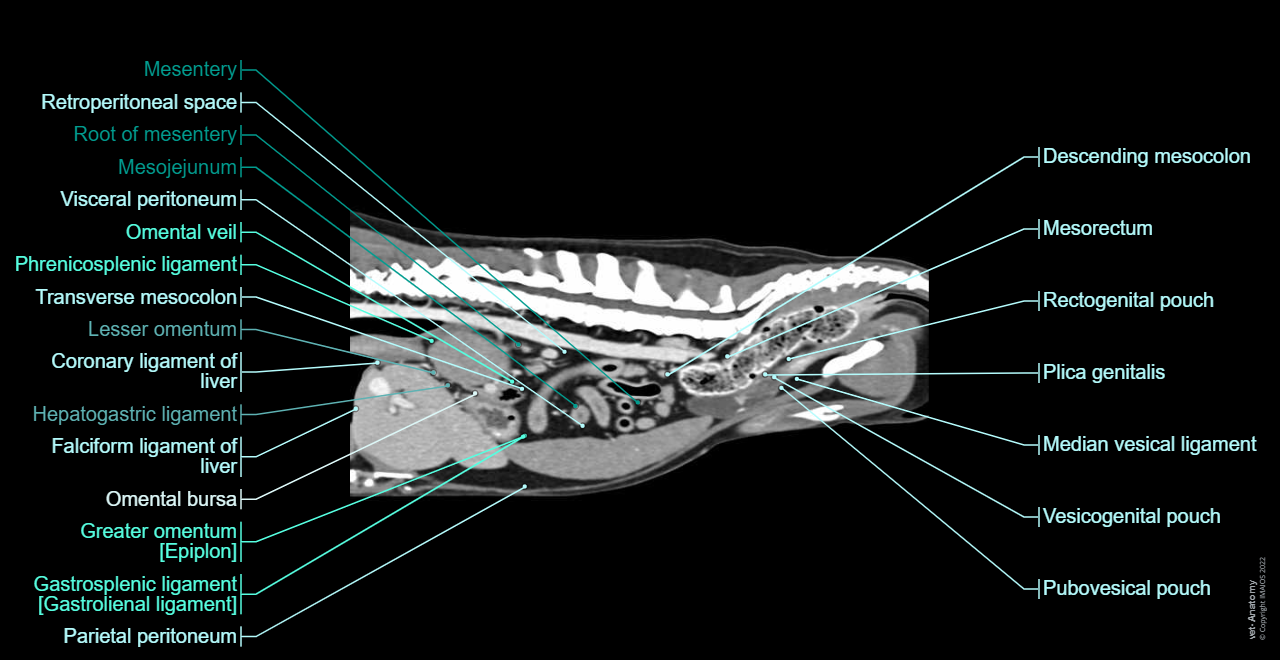

Dog - Peritoneal cavity: Peritoneum, Omental bursa, Greater omentum [Epiplon], Mesentery, Lesser omentum

Dog